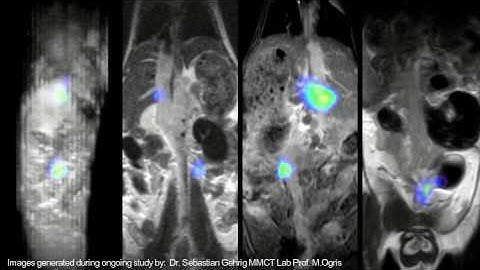

Simultaneous PET/MRI with the Aspect M7